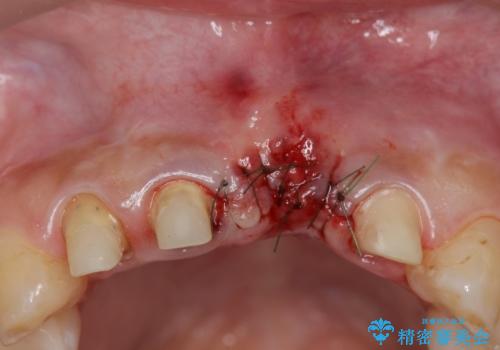

不良インプラントを除去し最終的にブリッジによる補綴で審美性の改善を行うこと、その準備として骨の造成・歯肉の移植による歯の欠損部顎堤のボリュームを維持・増大を計画します。

より審美的な改善を強く求められたため、インプラントを除去し可及的に欠損部顎堤を増大したのちブリッジによる審美改善を行いました。